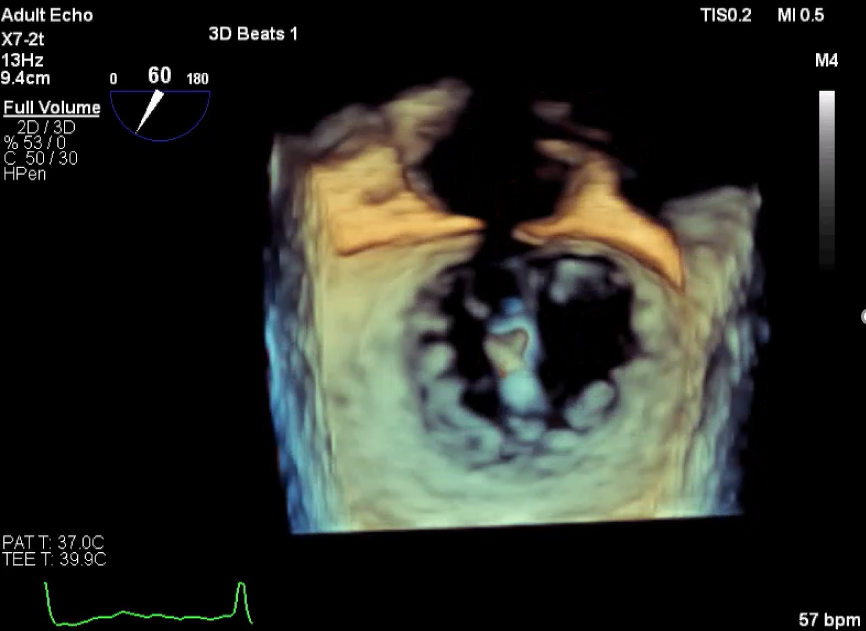

术前超声评估

术前超声诊断

LVOT-color:MR(重度),返流面积11.3cm2

肺静脉血流频谱呈收缩期反向

3D-color MV view:血流主要来源于2、3区

Qlab软件勾画估测瓣口面积约:6.16cm2

TEE LVOT切面返流量评估

TEE 4-Ch view返流量评估

术中超声

确定房间隔穿刺点:靠后

2D视图下测量大鞘长度2cm

3D视图打开夹子

X-plane:下第夹子尝试捕获2区

X-plane:测量前叶长25mm,后叶长14.2mm

X-plane:计算前叶捕获长度8mm,后叶捕获长度7mm

3D视图下观察二尖瓣双孔形态

3D-color:残余少量返流